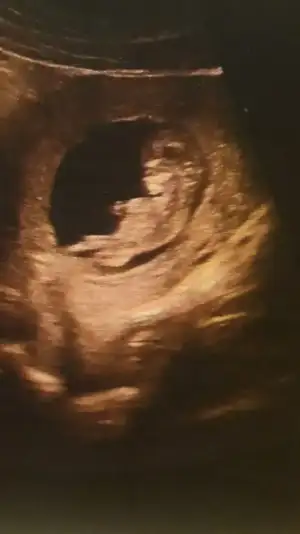

• Screenshot_20210112-232317_Gallery.webp

Screenshot_20210112-232317_Gallery.webp

18,5 KB · Görüntüleme: 83

• Screenshot_20210112-232255_Gallery.webp

Screenshot_20210112-232255_Gallery.webp

21,5 KB · Görüntüleme: 87